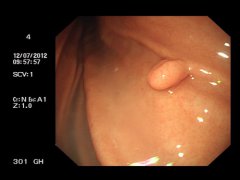

什么是胃息肉? 胃息肉(gastric polyp)是指胃黏膜局限性良性隆起病變。息肉這一名稱不表示它的病因及組織學(xué)構(gòu)造,只表示肉眼觀察到的隆起物。 胃息肉的病因: 目前病因不明。胃息肉是指起源...